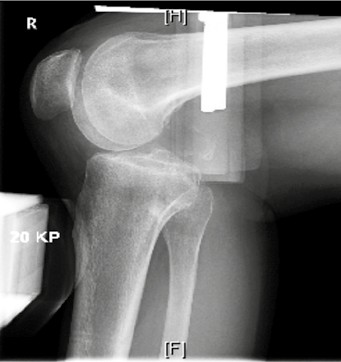

Zur quantitativen Erfassung der posterioren tibialen Translation haben sich gehaltene Röntgenaufnahmen bewährt (Abb. 4). Die posteriore tibiale Translation wird in diesen Aufnahmen im Vergleich zur Gegenseite am seitlichen Röntgenbild in Millimetern bestimmt. Ab einer posterioren Translation von 5 mm im Vergleich zur Gegenseite spricht man von einer „hinteren Instabilität“. Ab 12 mm besteht der Verdacht auf eine Begleitverletzung der posterolateralen oder posteromedialen Strukturen 33 34. Auch die Applikation einer nach anterior gerichteten Kraft hat in der Diagnostik hinterer Instabilitäten eine Bedeutung, da auf diese Weise eine fixierte hintere Schublade ausgeschlossen werden kann 35. Von einer fixierten hinteren Schublade spricht man, wenn trotz anterior gerichteter Kraft eine posteriore tibiale Translation besteht (Abb. 5). Liegt eine fixierte hintere Schublade vor, so muss diese vor einer operativen Rekonstruktion erst behandelt werden, sonst kann das Knie durch die ligamentäre Rekonstruktion nicht in die Neutralstellung gebracht werden. Hier hat sich die konservative Therapie mit einem „posterior tibial support brace“ bewährt (PTS Brace, Medi, Bayreuth).